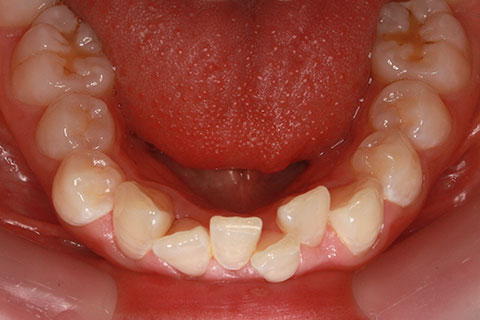

ハーフリンガル矯正3:上の歯のみ舌側矯正で治療(矯正期間24ヶ月)

治療前

治療中(開始直後)

治療中(開始半年後)

治療後

- 年齢・性別

- 25歳女性

- 治療期間

- 2年0ヶ月

- 抜歯

- 上下4番抜歯

- 治療費

- 110万円

- 備考

- 治療内容

- 施術の副作用(リスク)

- 表側矯正と比較して、力学的な操作性が複雑なため、ボーイングエフェクトを起こしやすい。